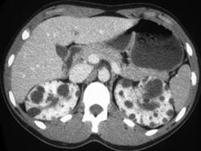

问题 女,34岁,血肌酐、尿素氮增高,请根据所示图像,选择最可能诊断 ( )

选项 A、双侧多发性肾囊肿 B、多发囊肿性肾发育不全 C、多囊肾 D、囊性肾癌 E、双肾脓肿

答案 C